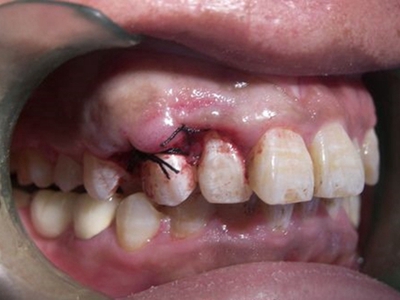

对于牙龈瘤可在局麻下手术切除,切除必须彻底,否则易复发。如果复发,仍可手术切除。多次复发者,即使病变波及的牙无松动,也应将牙拔除,防止再发。